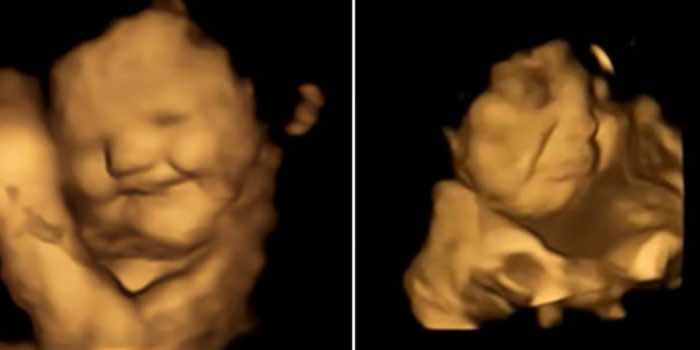

正如已经指出,胎儿开始妊娠14周后发展的味蕾。因此,在研究研究中,大约100名母亲在怀孕最后三个月了。形成了共三组,包括母亲使用超声波没有消费任何形式的食物。第二和第三组包含那些孕妇食用甘蓝或胡萝卜粉,太,大约20分钟前超声波。结果是迷人的。你可以看到在下面的图片中,胎儿在第二或第三组开始回应他们的母亲的味道通过面部表情。它是可爱的,不是吗?

加上这一点,研究人员继续为约25分钟超声波的过程,这样他们可以有效地、准确地扫描所有的面部表情和动作。正如你所看到的图片,胎儿暴露于甘蓝演示了一个哭脸,而胎儿母亲食用胡萝卜显示响应的形式“笑的脸。“这是难以置信的,但科学家仍模糊这迷人的现象背后的原因。